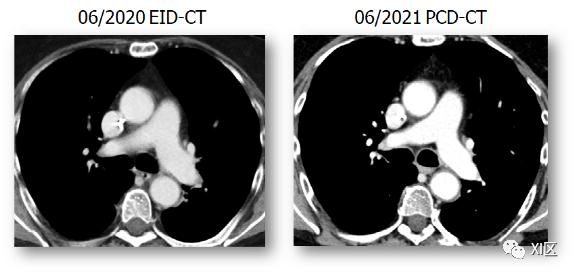

同一位患者相隔1年扫描,具有相同的BMI和相同剂量的碘造影剂。注意使用相同窗中心/窗宽的PCD-CT系统上的碘对比度更亮。当使用含碘造影剂时,这一点尤其明显,因为碘由于造影血管的高X射线密度而产生量子衰减,尤其是在CTA中。碘的吸收相对较高,具有33.2keV的“K-edge”(X射线吸收的K壳层结合能),因此光子计数探测器的这一优势特别突出,并导致更高的碘对比度和更高的对比噪声比。